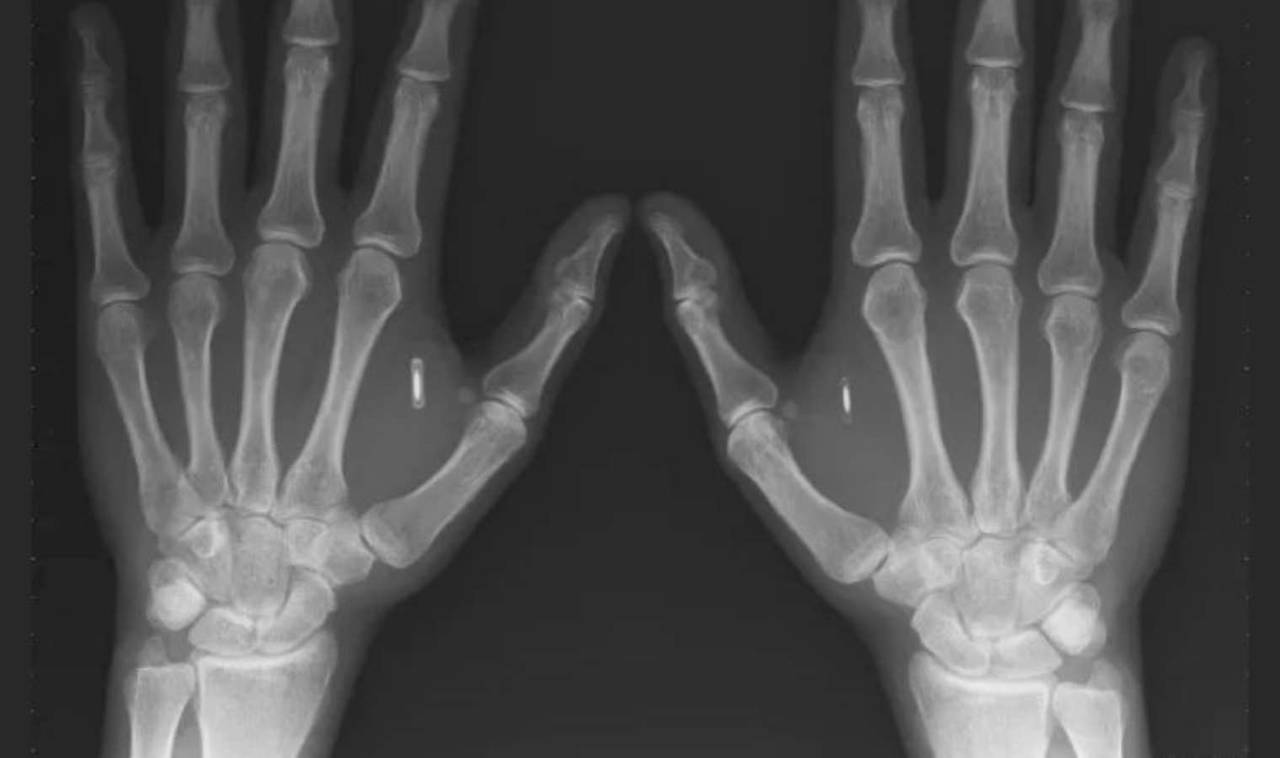

Yazılım mühendisi Miana Windall’ın derisinin altında mıknatıslardan RFID teknolojisine kadar değişen yaklaşık 25 implant bulunuyor. Engadget ile görüşen mühendis, “Çoğunlukla gerçekten fark edilmiyorlar” diyor. Windall, geçtiğimiz hafta DEF CON güvenlik konferansında, implantlarla nasıl ilgilenmeye başladığından ve onları eski ofis binasını taramak gibi kişisel kullanım için programlama deneyiminden bahsetti.